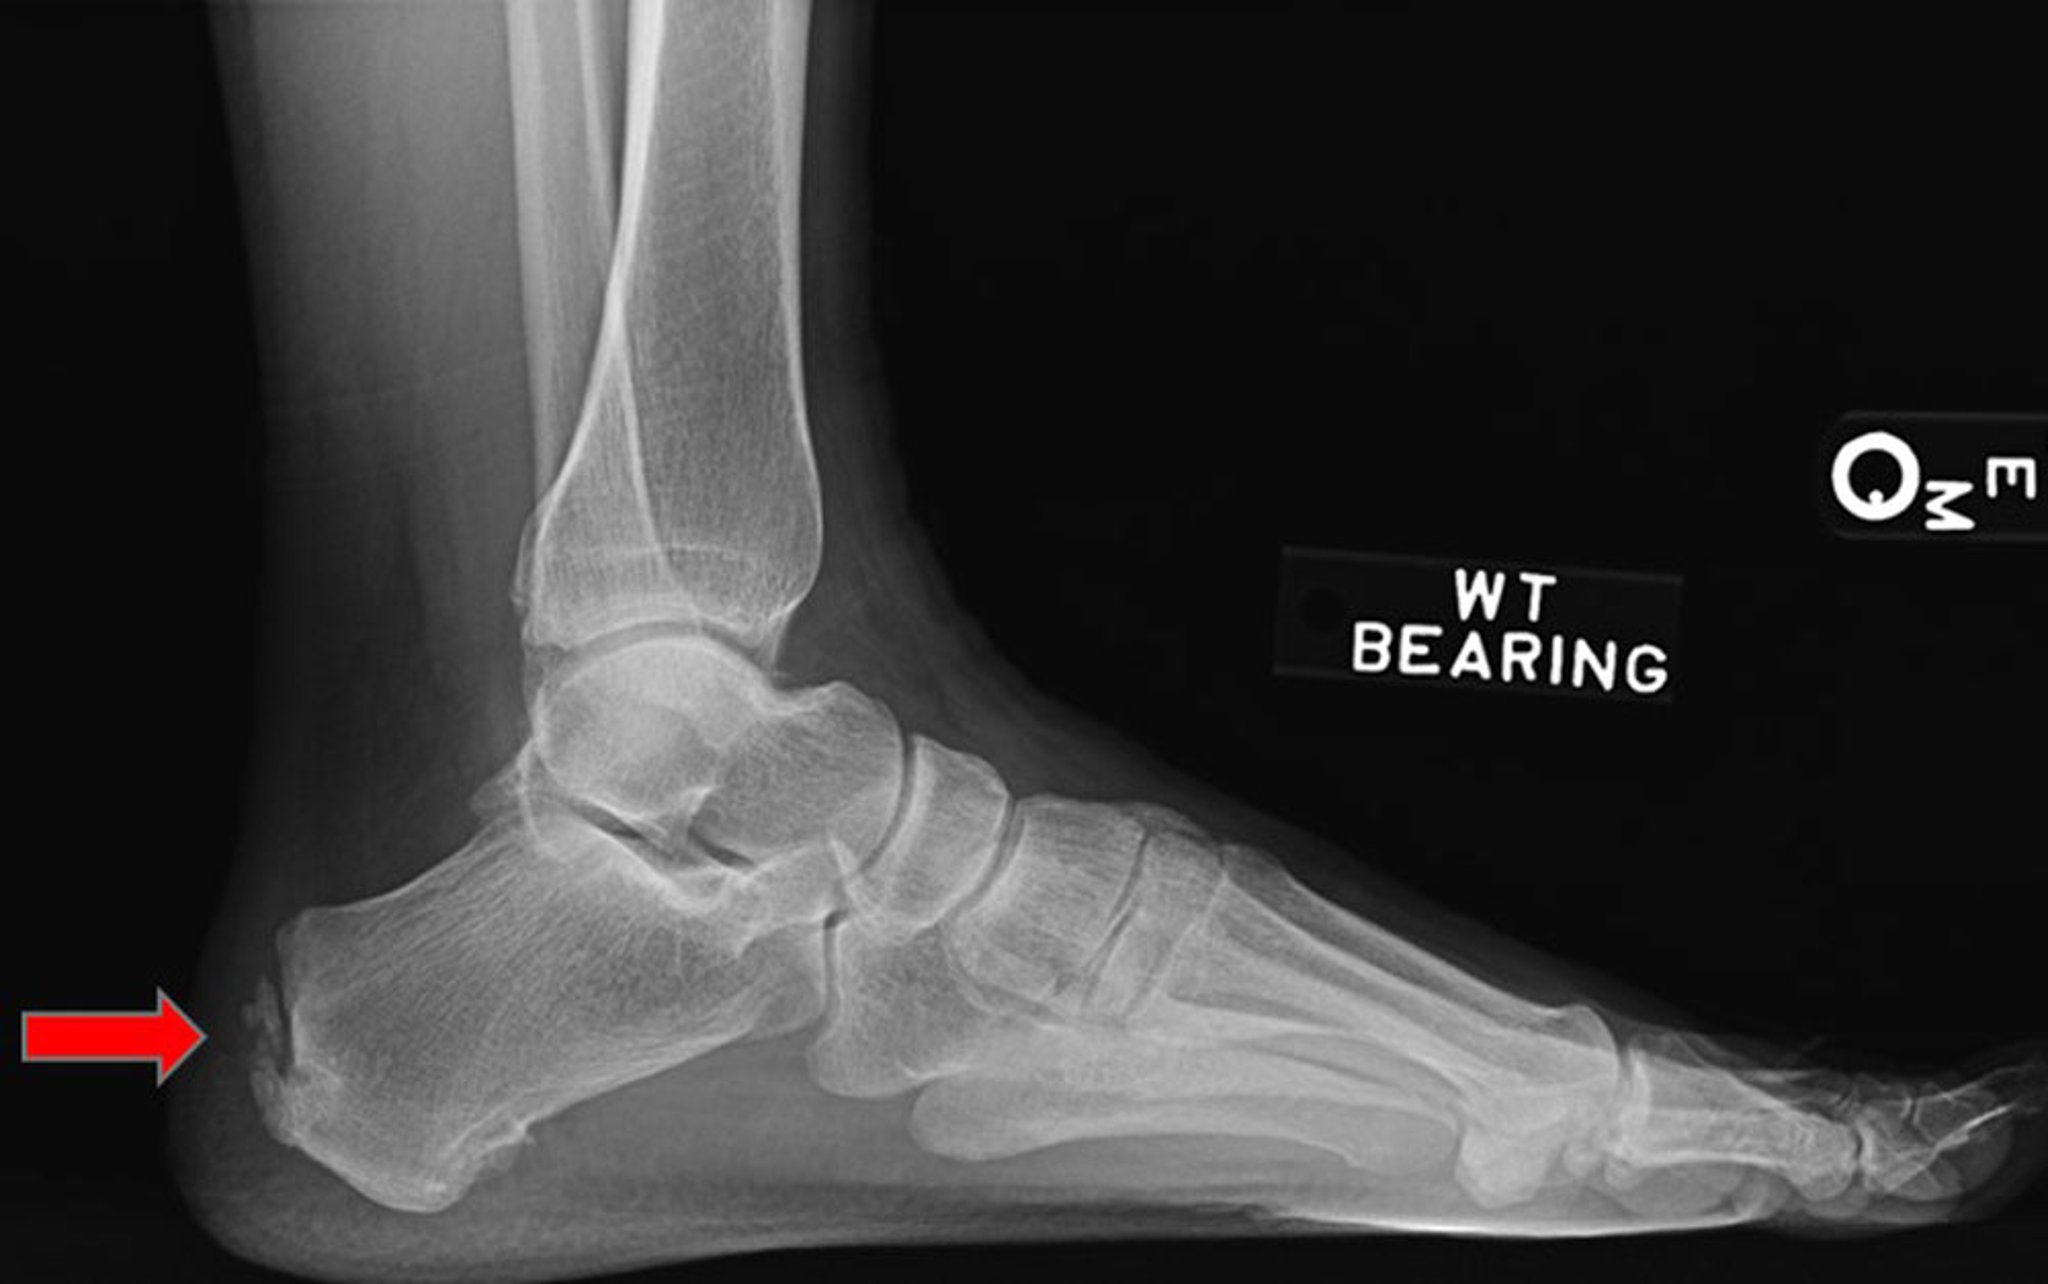

跟腱附着点病

该侧位X线片显示跟腱附着点病变(箭头所示)。

Image courtesy of James C.Connors, DPM.